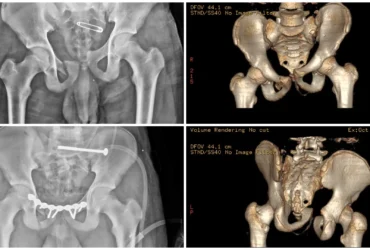

●DEFORMITY CORRECTION

●COMPLICATED FRACTURES

●FAILED FRACTURES

●TRAUMA CARE WITH DEEP ACCURANCY

We Provide Orthopedic Service by Experience Doctors

We has a dedicated multidisciplinary team that cares for and surgically repairs acute fractures for patients of all ages. We offer expertise in fractures of the hip, arm, leg, hand, foot and ankle.